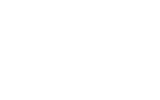

Congenital heart defects

A congenital heart defect (CHD) is a heart problem that a baby has at birth. It is caused by abnormal formation of the heart during growth in the womb. There is no known reason for it.

Most cases of congenital heart defect have no known cause. But some types of congenital heart defects occur more often when the mother comes in contact with some types of dangerous substances in the first few weeks of her pregnancy.